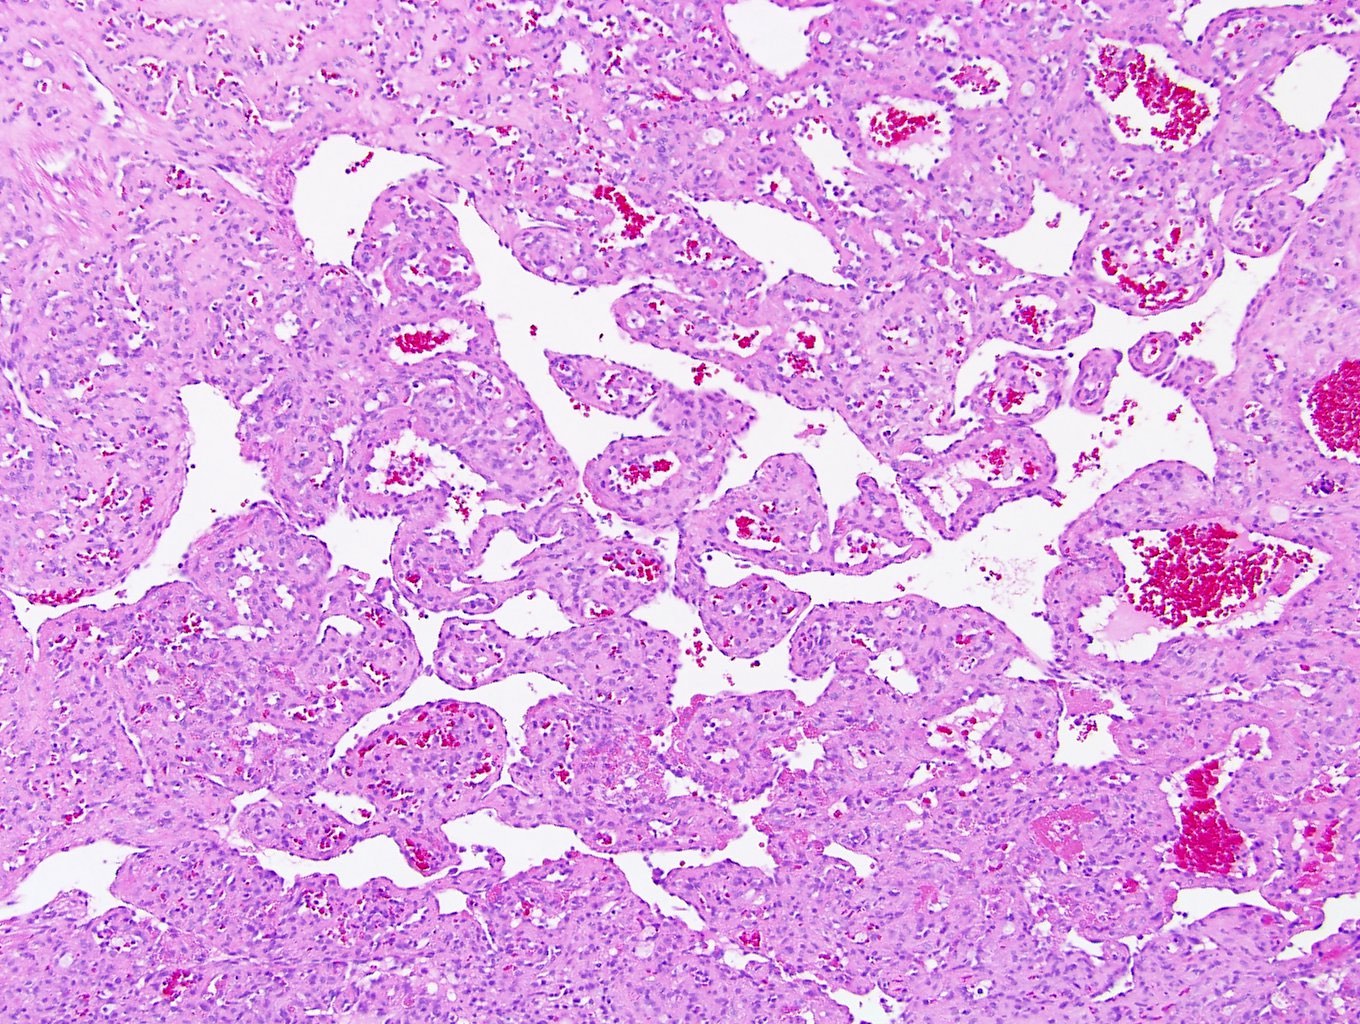

Microscopic (histologic) description

- Circumscribed, unencapsulated proliferation of irregular, blood filled vascular spaces lined by a single layer of endothelial cells

- Anastomosing hemangioma (AH):

- Capillary sized sinusoidal vessels with anastomotic arrangement

- Scattered hobnail endothelial cells

- Extramedullary hematopoiesis, fibrin thrombi, extensive perirenal fat entrapment, intravascular growth and mast cells may be seen (Histopathology 2014;65:309)

- Cytologic atypia and mitotic activity rare

- Regressive changes, including hyalinization, cystic changes and fatty overgrowth (Histopathology 2014;65:309)

Microscopic (histologic) images